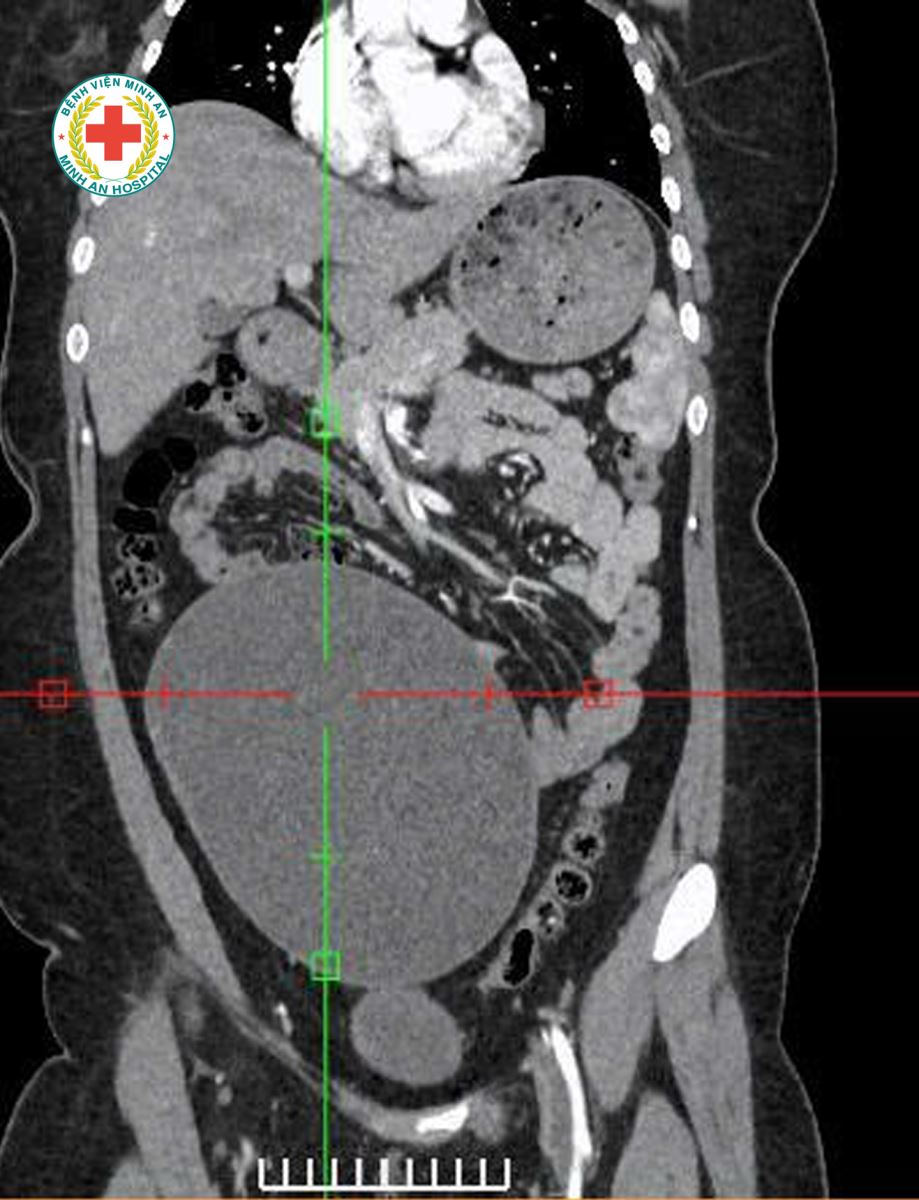

Khoa Sản – BVĐK Minh An vừa tiếp nhận tiếp nhận một trường hợp đặc biệt: U nang buồng trứng kích thước rất lớn, tương đương thai khoảng 20 tuần tuổi, người bệnh gần như không có triệu chứng rõ ràng, chỉ xuất hiện ra máu bất thường ngoài chu kỳ. Điều đáng chú ý là bênh nhân mới 22t, chưa từng sinh nở.

Ngay sau khi thăm khám và chẩn đoán, ekip Khoa Sản do BS Phan Thị Xuân – Phó Trưởng khoa trực tiếp thực hiện đã nhanh chóng đưa ra phương án tối ưu: Phẫu thuật nội soi bóc tách khối u, bảo tồn tối đa buồng trứng, giữ gìn khả năng sinh sản cho người bệnh. Ca phẫu thuật diễn ra an toàn, nhẹ nhàng, người bệnh hồi phục tốt sau mổ.